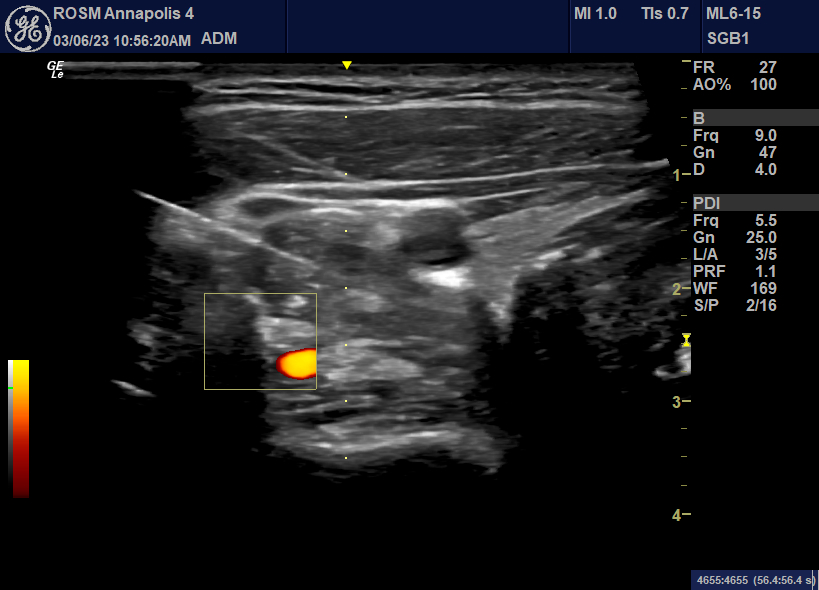

PATIENT TESTIMONIALSUltrasound guided SGB is less painful, more effective and does not expose patients to ionizing radiation of the xray.